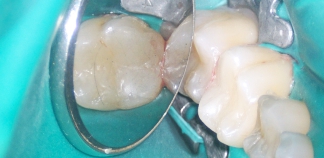

Жалобы на периодически ноющие боли при накусывании в зубе.

Пациенту 35 лет.

Как лечили

Удалена старая пломба, пролечен периодонтит. Запломбированы корневые каналы. Установлен стекловолоконный штифт и проведено культевое восстановление. Направлен на установку коронки.

Лечение проведено за три визита.